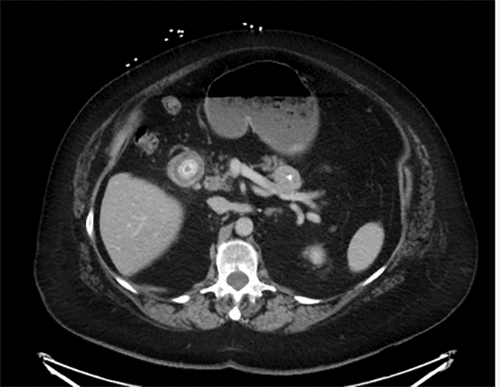

A computed tomography (CT) scan demonstrated a 2 cm rounded, radiopaque structure within the second portion of the duodenum, obstructing the outflow of stomach contents. The stomach appeared moderately dilated. The gallbladder was not clearly visualized, suggesting inflammation with erosion into the duodenum, stomach, or hepatic flexure. The majority of gallstone impaction sites are in the ileum related to the smaller diameter of the distal small bowel. Mild intrahepatic biliary ductal dilation, most significant in the left hepatic lobe, was observed (Figures 1 and 2).

Figure 2. Axial CT Imaging of Gallstone Ileus. Published with Permission

Axial CT image demonstrating a gallstone within a small bowel loop in the right upper quadrant